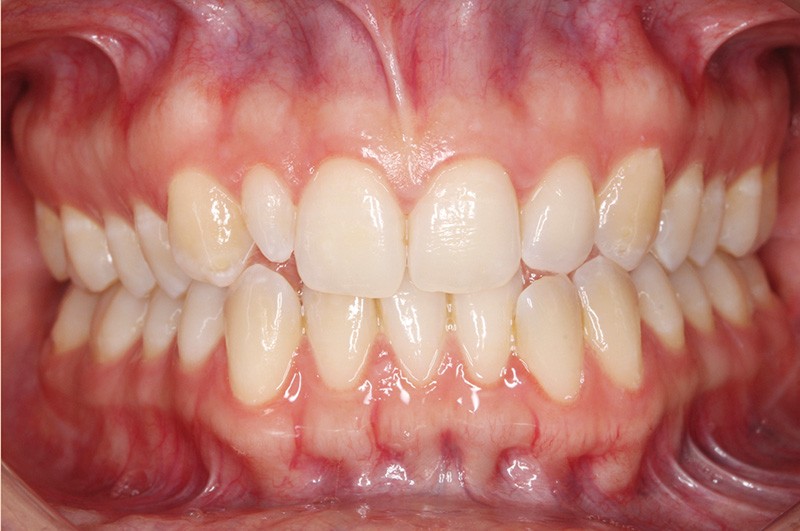

Elle présente une classe I dentaire en denture adulte. Son sourire est perturbé, notamment par la microdontie de son incisive latérale maxillaire droite (la 12). On constate un encombrement modéré au maxillaire (bimarginotopie mésio-palatine et disto-vestibulaire de 13) et plus marqué à la mandibule (monomarginotopie mésio-vestibulaire de 32 et de 43) (fig. 1-6).

Les milieux inter-incisifs ne sont pas coordonnés, à torts partagés, avec une légère déviation à droite du milieu inter-incisif maxillaire et une déviation plus marquée à gauche du milieu inter-incisif mandibulaire ainsi que du point menton. 32 et 33 présentent une tendance à l’exoclusion.